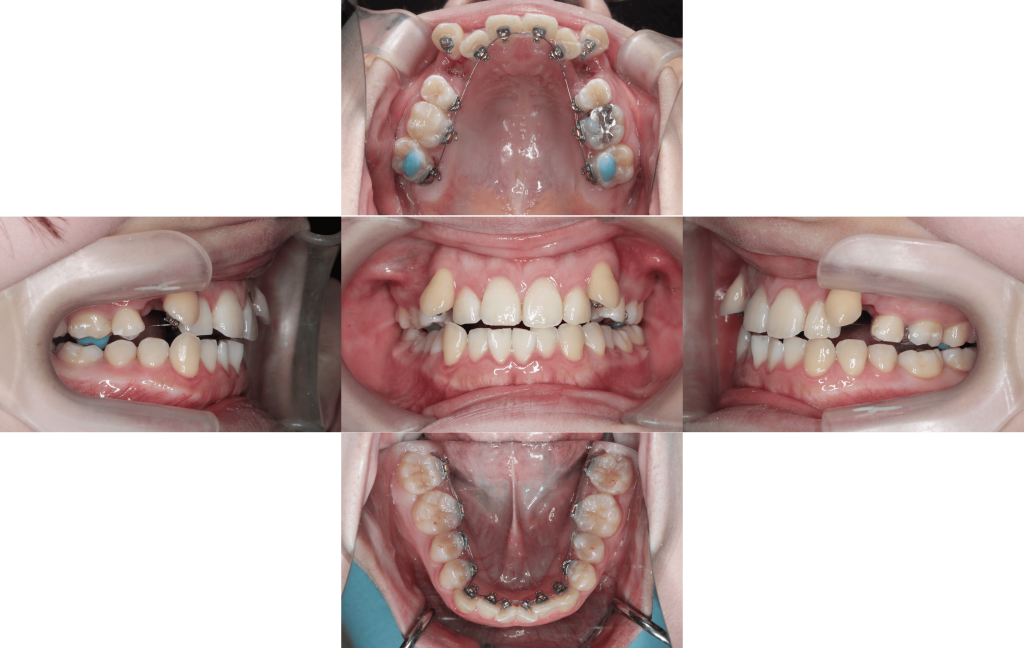

約2か月経過